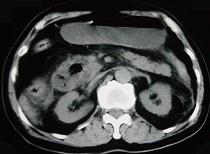

问题 男,78岁,阵发性上腹部疼痛10年伴呕吐,加重1年,影像检查如下图,应诊断为 ( )

选项 A、十二指肠结核 B、肠系膜上动脉压迫综合征 C、十二指肠憩室 D、十二指肠淋巴瘤 E、十二指肠癌

答案 C